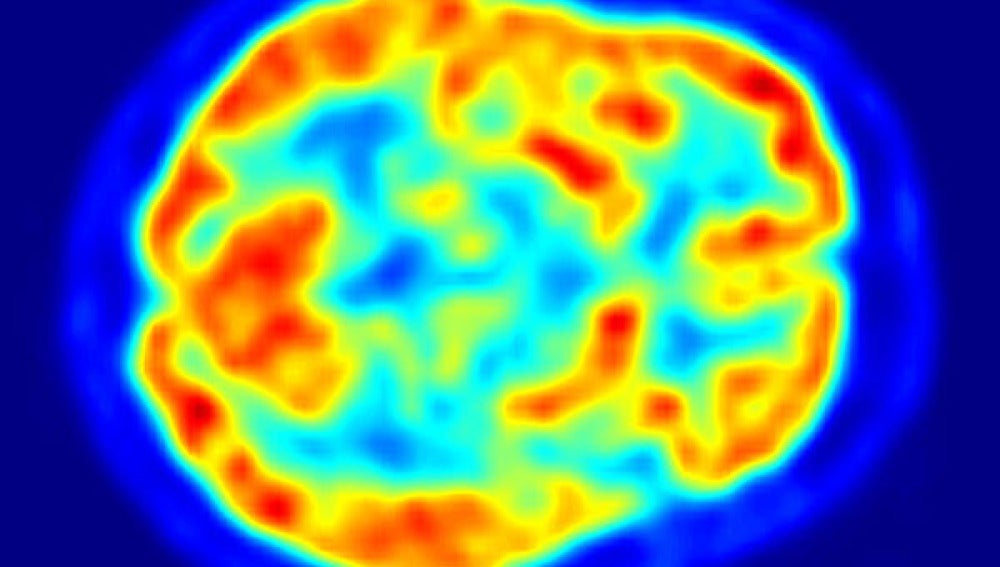

Un cerebro a través de un PET Wikipedia

Pero en el caso de la medicina molecular, el armamento indicado son las máquinas PET que, a diferencia de los TAC -Tomografías Axiales Computerizadas- son Tomografías por emisión de positrones. Funcionan por tanto detectando en una zona del cuerpo un haz de positrones, elementos de idéntica masa y carga que el electrón, pero de signo contrario, que la máquina visualiza con gamas de colores para mostrar nuestra actividad metabólica.

La explicación médica del funcionamiento de la FDG es que las células que empiezan a reproducirse de forma anómala al formarse el tumor, como todas las células, se alimentan de azúcar, por lo tanto habrá un mayor consumo de azúcar donde haya más células y esté la probable localización del tumor. La FDG lo que hace es enviar una 'baliza' a las máquinas tipo PET que permite ver no sólo dónde está, sino lo rápido que es el consumo de esa glucosa marcada radiactivamente y, por tanto, lo virulento que es el tumor.

Por diferenciar los procesos mecánicos, en una máquina de rayos X el emisor -la fuente- y el detector son externos al paciente. En una máquina PET la máquina hace de detector, el emisor es el propio paciente y la fuente es el medicamento radiactivo que se le injecta y se fija en las célulares tumorales.